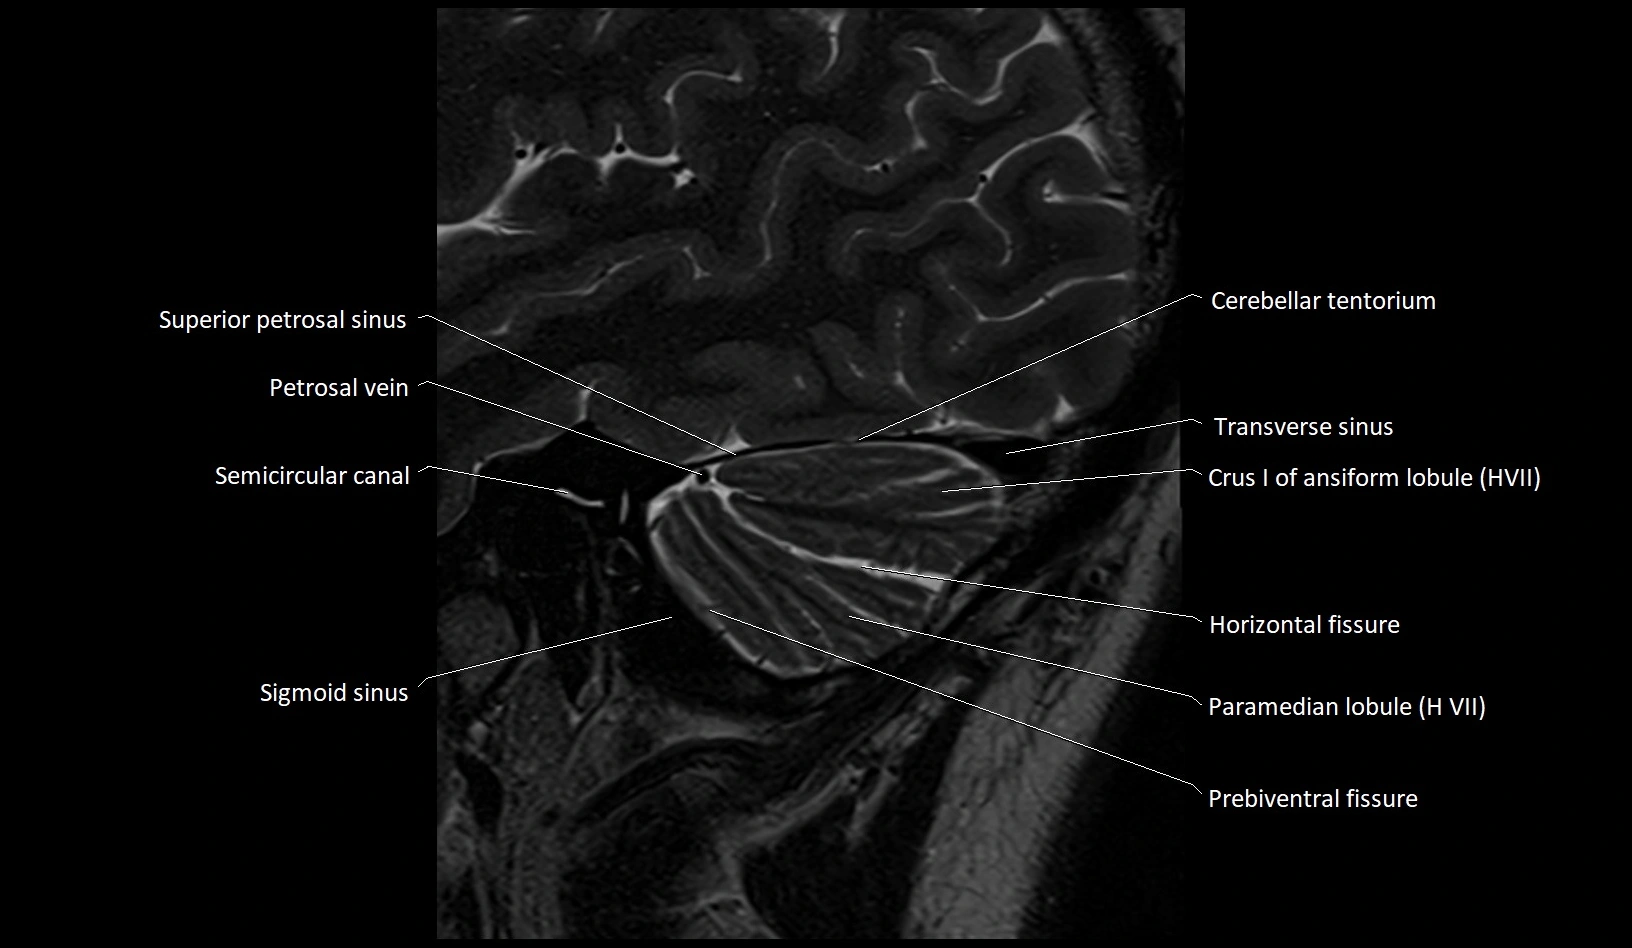

MRI images